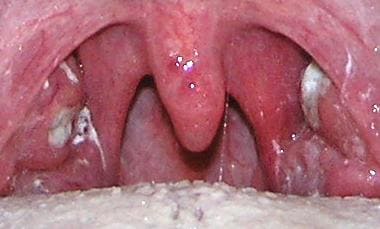

Боль в шее и лопатках может возникать при воспалительных заболеваниях лор – органов – ангина, фарингит, ларингит, трахеит, заглоточный абсцесс.

Тонзиллит

Температура, боли в горле, боли при глотании, изменение голоса, «заложенность» горла должны привести больного к ЛОР врачу. Острый отит может сопровождаться односторонними болями в шее.

Боли в шее могут быть при шейном лимфадените – пальпируется увеличенное болезненное образование на шее, мягкое, «катающееся» под пальцами, сопровождающееся повышением температуры. Чаще возникает как осложнение воспалительных заболеваний полости рта, лор – органов. Требуется тщательное обследование и лечение очага инфекции. Лимфаденит, при прогрессировании развивается периаденит, абсцесс, при прорыве абсцесса флегмона…сепсис.

Шейный лимфаденит при инфекционном мононуклеозе